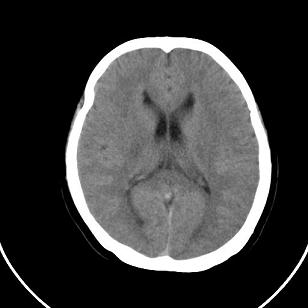

双侧脑室边缘呈波浪样,没有见过?

双侧脑室外缘灰质密度结节应该是尾状核的体部;枕大池前缘受压前移位,考虑囊肿

不知患者有无临床症状,双侧侧脑室边缘不规则,呈波浪状,考虑脑室周围白质软化症可能性大

影像学表现:软化灶分布于半卵圆中心和脑室周围白质,呈斑片状或长条状,多为双侧分布,脑室扩大,且脑室缘不规整。这是本症在影像学上的特点。

这个病例不符合脑室周围白质软化症

是不是应该考虑结节性硬化或者灰质移位,建议mri

支持灰质移位,mri检查有必要.枕大池蛛网膜囊肿.

1)脑灰质异位。2)双侧枕部颅骨内板下方类似扇形及弧形脑脊样低密度影;鉴别于巨大枕大池与蛛网膜囊肿之间。建议必要时行进一步检查。